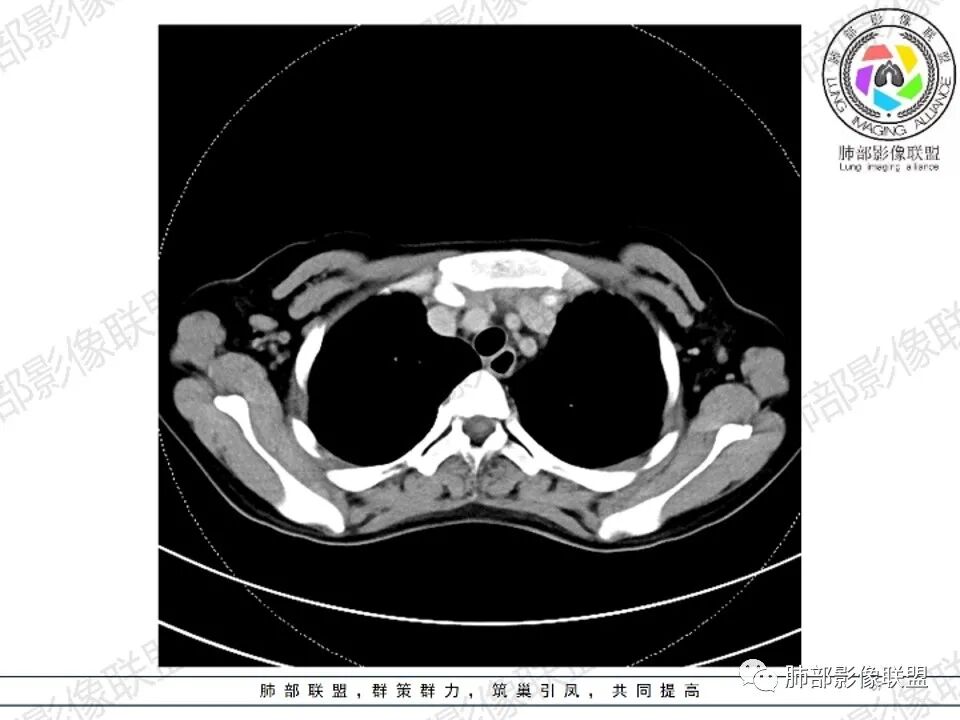

年轻女性,贫血伴乏力,前纵隔占位,多发结节融合成块,爬孵感,边界模糊,不均匀强化,中心坏死,内可见血管造影,部分侵犯心包,双侧腋窝多发肿大淋巴结,首先考虑淋巴瘤

年轻女性,贫血,CT示前纵隔团片状软组织占位,多结节堆积感,塑形生长,边界欠清,包绕大血管及心包,增强明显不均匀强化,内见血管漂浮。纵隔4R,5,7区及双侧腋窝多发肿大淋巴结,综合考虑为淋巴瘤可能

前纵隔和双侧腋窝多发的淋巴结肿大,前纵隔为甚,融合呈中等强化,部分坏死呈低密度,包埋肺动脉主干和左心缘,融合斑块状,内见血管飘浮特点,前纵隔脂肪间隙混浊,首选淋巴瘤!

4.双侧腋窝区见增大淋巴结,边界清楚。